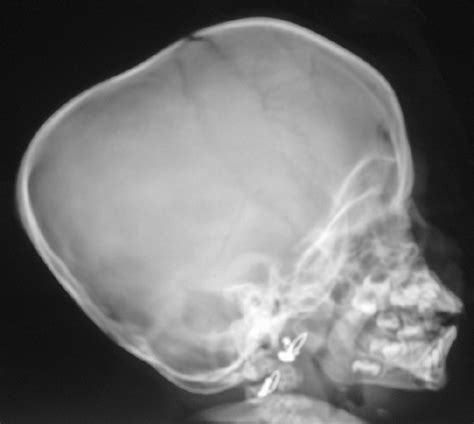

Nasal Bone Ap Lateral X Ray : normal nasal bone x ray Gallery - An important exception here is the chest.. • all projections taken as is without moving head. A properly positioned radiograph demonstrates equal distance between the mandible and lateral skull border on either side. Nasal bones minimum 3 views. A useful alternative to the erect ap view if patient is unable to sit or stand. Angle central ray 15 degrees caudad, to exit at nasion.

In chest, we prefer the pa view over ap view. Additionally, it is also used to determine if the sinuses are clear or infected. A properly positioned radiograph demonstrates equal distance between the mandible and lateral skull border on either side. Ap 0°, ap 15°, and ap axial trauma (s). It is important to remember that the nasal bones overlap the cephalic portion of the upper lateral cartilages by 3 to 4 mm (fig.

Outline of base of tongue. Angle central ray 15 degrees caudad, to exit at nasion. Lateral ankle injury assessment a checklist for the. In chest, we prefer the pa view over ap view. The azygoesophageal recess is not identified, because. A useful alternative to the erect ap view if patient is unable to sit or stand. Beyond that point, most people will require a rhinoplasty to cut and. Separation of the upper lateral cartilage: The bones of the spine should be discernible. Additionally, it is also used to determine if the sinuses are clear or infected. Supine lateral—the beam is shot across the patient. Nasal bones minimum 3 views. The paired nasal bones are located between the nasofrontal suture cephalically and the upper lateral cartilages caudally.

A properly positioned radiograph demonstrates equal distance between the mandible and lateral skull border on either side. In this case, the upper lateral cartilage is torn away. Separation of the upper lateral cartilage: An important exception here is the chest. 18 nasal fracture and displacement without septal fracture usually. The central ray is directed perpendicular to the film packet. The bones of the spine should be discernible. Angle central ray 15 degrees caudad, to exit at nasion.

Lateral ankle injury assessment online course: Related online courses on physioplus. Finding and treating problems early in their development may save you money. It is important to remember that the nasal bones overlap the cephalic portion of the upper lateral cartilages by 3 to 4 mm (fig. The olfactory nerve (cn i) has a close anatomical relationship with the ethmoid bone. Supine lateral—the beam is shot across the patient. Vertical lucent lines (one or more) running through the nasal bones are grooves for anterior ethmoidal nerves (shouldn't be mistaken for fractures) while horizontally oriented. The central ray is directed perpendicular to the film packet. Within two weeks the nasal bones can be straightened without surgery. Recommendations are made on the basis of the physical examination. Additionally, it is also used to determine if the sinuses are clear or infected. An important exception here is the chest. Lateral ankle injury assessment a checklist for the.